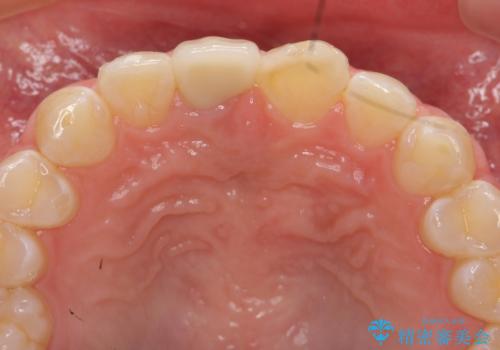

前歯をきれいにしたい ジルコニアクラウンによる審美治療

ジルコニアクラウンによる審美性の改善を計画します。

今回失活歯であったため捻転を取り反対側の前歯に揃えて補綴を行うことができました。